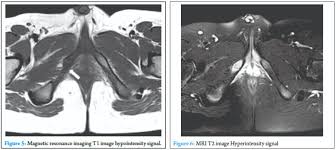

The different characteristics by images from simple radiography computed tomography MRI and bone. Van Neck-Odelberg disease is a benign process that develops in children between the ages of 4 and 16 years. Van Neck-Odelberg disease or ischiopubic osteochondritis is a rare cause of pain in the pediatric pelvis due to late closure in synchondrosis ischiopubic whose main symptom is an asymmetric pain that can cause a limitation in movement or limp.

It is a temporary joint which is slimming to obliterate a bone fusion with skeletal maturation. Se observa un engrosamiento con edema óseo a nivel de la sincondrosis isquiopubiana derecha adyacente al músculo obturador externo flecha. The van Neck-Odelberg disease is hyperostosis of ischiopubic synchondrosis IPS.

Se conoce entonces como síndrome de Van Neck-Odelberg a la osteocondritis isquiopúbica que se desarrolla en niños entre los 4 y 16 años. The literature to date contains fewer. A Case of van Neck-Odelberg Disease and Intermittent Overuse Injury Abstract. Van Neck-Odelberg disease is a benign process that develops in children between the ages of 4 and 16 years. Patients typically complain of vague groin or buttock pain. The different characteristics by images from simple radiography computed tomography MRI and bone. It is a temporary joint which is slimming to obliterate a bone fusion with skeletal maturation. Left leg dominant patient presented with pain in groin and limping with left leg dominance. Differential diagnosis such as stress fractures osteomyelitis tuberculosis post-traumatic osteolysis or any neoplasia is need be ruled out to arrive at diagnosis.

The synchondrosis ischiopubic SIP is the cartilaginous union between the lower ischium and pubis branch in infancy. BACKGROUND Van Neck disease VND is a benign skeletal abnormality of children involving a hyperostosis of the ischiopubic synchondrosis IPS seen on radiographs. Van Neck-Odelberg disease is a syndrome characterized by an atypical ossification pattern of the ischiopubic synchondrosis. The van Neck-Odelberg disease is hyperostosis of ischiopubic synchondrosis IPS. Der Morbus van Neck oder Morbus Odelberg-van Neck ist eine seltene Form der aseptische Knochennekrose im Bereich des Beckens Synchondrosis oder Osteochondrosis ischiopubica. In van Neck-Odelberg disease an enlarged anatomical structure called ischiopubic synchondrosis is susceptible. However the radiological findings corresponded instead to van NeckOdelberg diseasea rare benign aseptic bony necrosis of the ischiopubic.